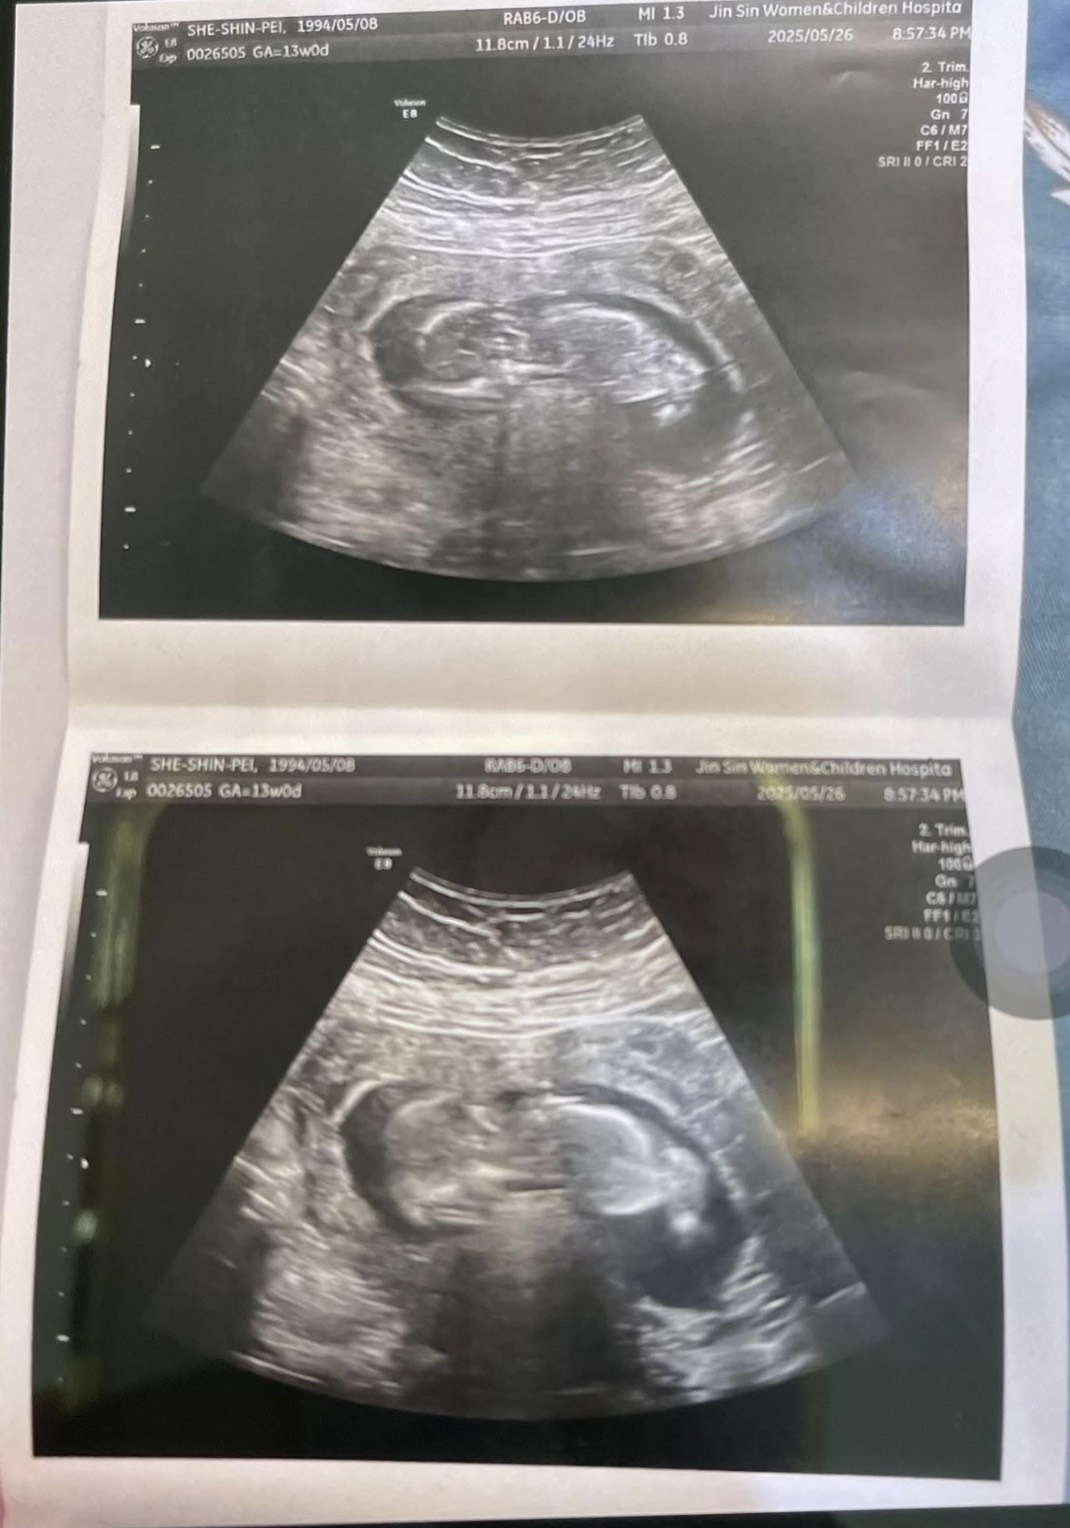

Y小姐體態較豐潤,舌紅胎白膩,經常食後腹脹、腹瀉,每到月經前後分泌物異常增多,經過詳細診察辨證後為痰濕內阻型,給予適合之中藥治療後,去除痰濕,恢復規律排卵,月經規則來潮。搭配測量基礎體溫預測排卵期,進行計畫性懷孕,自然懷孕成功,懷孕後持續服用中藥安胎,目前胎兒已經超過三個月大,穩定成長中。

圖片來源:Y小姐提供。